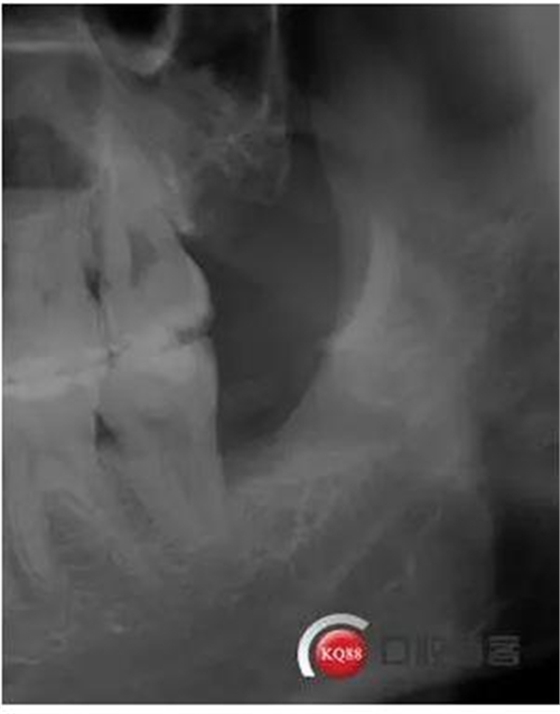

檢查:口內(nèi)可見38未完全萌出,無松動(dòng),周圍牙齦顏色正常,叩診(—)觸診(—),X線顯示近中阻生,雙根

診斷:阻生齒

治療方案:建議拔除

處理:治療計(jì)劃及費(fèi)用已說明,知情同意后,排除拔牙禁忌癥:口腔黏膜消毒,左下頜阻滯麻醉成功后,切開翻瓣,渦輪機(jī)去除近中阻力,向近中挺出患牙,拼對(duì)牙體完整,清創(chuàng),置明膠海綿,縫合傷口,咬棉球壓迫止血